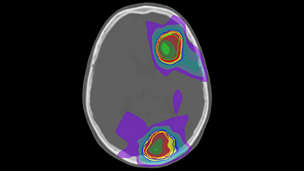

MRCAT Brain

MRCAT Brain clinical application allows the use of MRI as the primary imaging modality for radiotherapy planning of primary and metastatic tumors in the brain without the need for CT. Detailed anatomical information for contouring and attenuation maps for dose calculations are both obtained from a single, submillimeter resolution 3D T1W mDIXON MR sequence. Artificial Intelligence (AI) is used for fast computation of continuous Hounsfield units directly on the MR console.